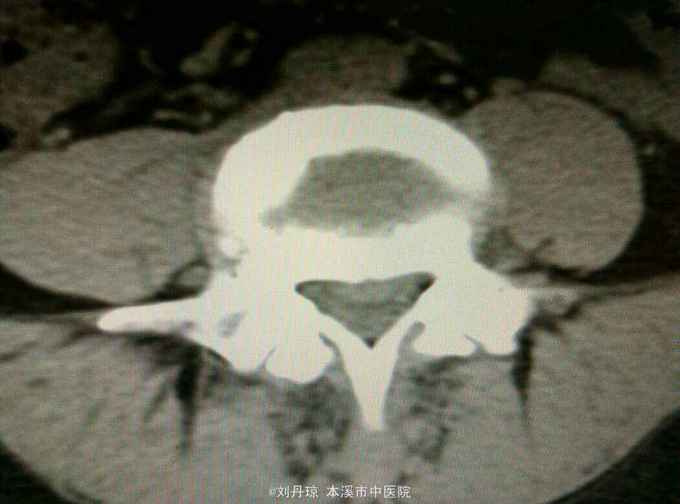

腰部疼痛伴右下肢放射痛麻木感1年,加重1月。患者1年前劳累后感到腰部疼痛伴右下肢放射痛麻木感,近1月病情加重来诊。

查体:L3—S1棘突右旁压痛阳性。直腿抬高实验左70度,右40度。 直腿抬高加强实验左侧阴性,右侧阳性。腰椎功能障碍。 辅查:CT: L3—S1椎间盘突出。

诊断:腰椎间盘突出症 治疗:针灸、雷火灸、中药熏药治疗、小针刀治疗、骶管注射治疗、营养神经药物治疗、脱水药物治疗,当归地黄饮加味。